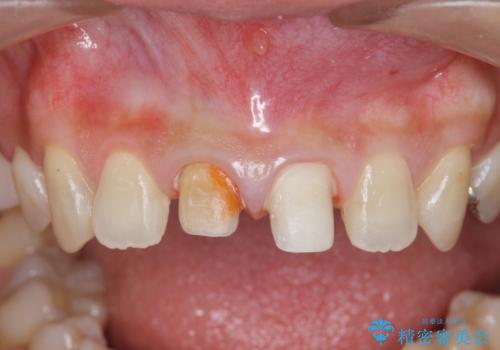

- 「 以前神経を取った歯の変色が気になる。前歯をきれいにして欲しい。」と治療を希望され来院されました。

目立つ上顎前歯に変色・大きな虫歯治療痕が見られ、審美障害を引き起こしています。

虫歯の徹底的な除去、根管治療を行いセラミック治療に入る前の環境をしっかりと整えたのち審美的なジルコニアセラミックで治療を仕上げました。